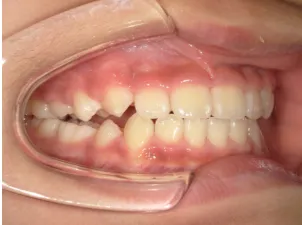

治療後⑨中2(13y11m):モノブロック装置継続中

咬み合せも安定していて、口元の突出・口唇閉鎖不全も改善

*レントゲンや歯の萌出状況などから成長が終了していると考えられるため、現在残っている隙間や上下正中の不一致を改善するためマルチブラケット法へ移行するか検討中です。

治療は歯並びや口元などの状態から非抜歯治療で行う予定です。